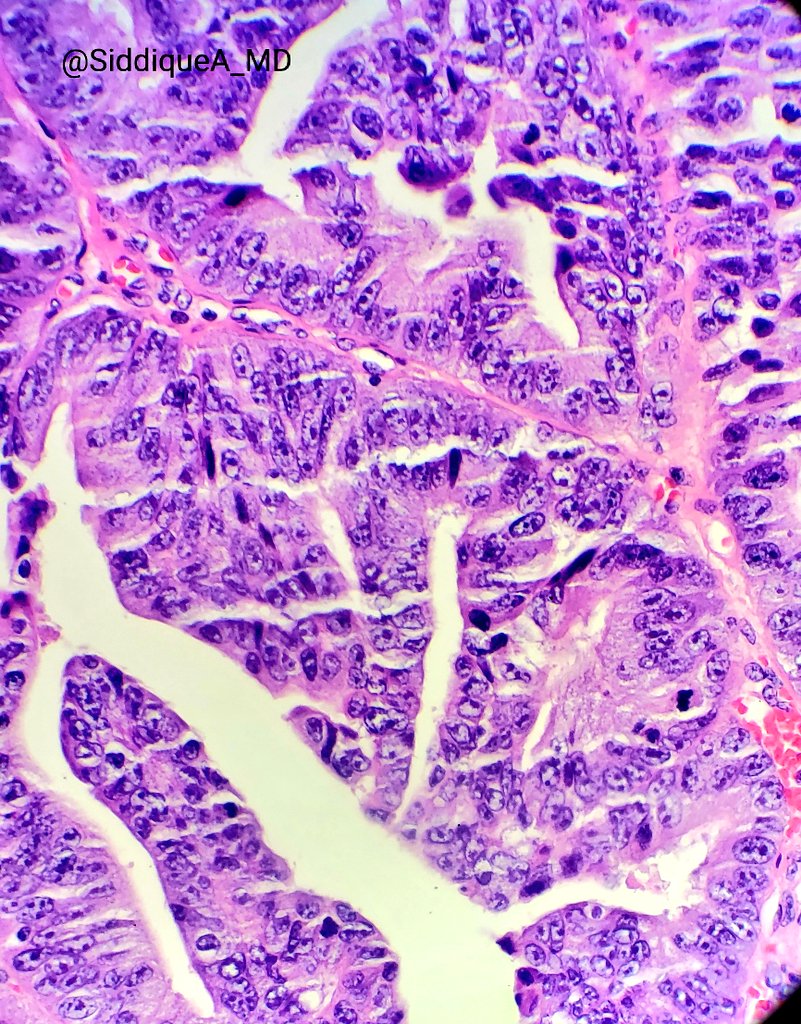

I'm obsessed with papillary lesions of the pancreatobiliary tract these days :D beautiful case of intraductal papillary neoplasm of cbd. No invasion.

#gipath#papillary#biliary pic.twitter.com/p2O4dNwp2J

Prikaži ovu nit -